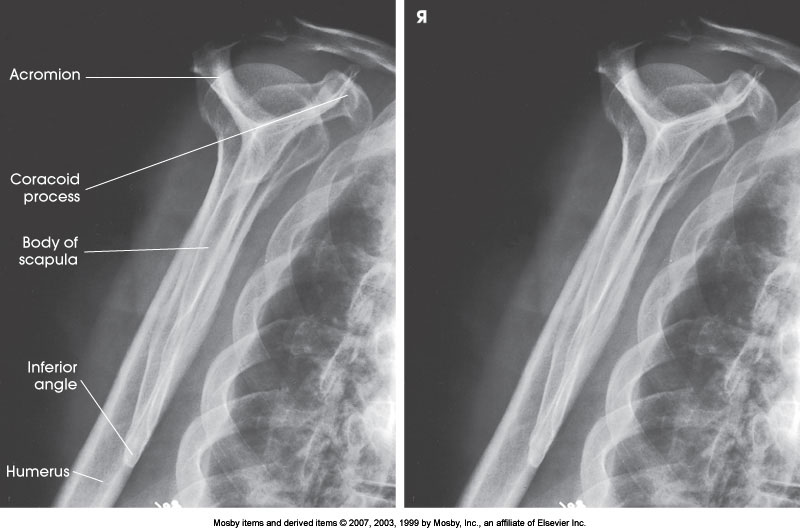

PA Oblique Shoulder (Y-View)

What position is demonstrated?